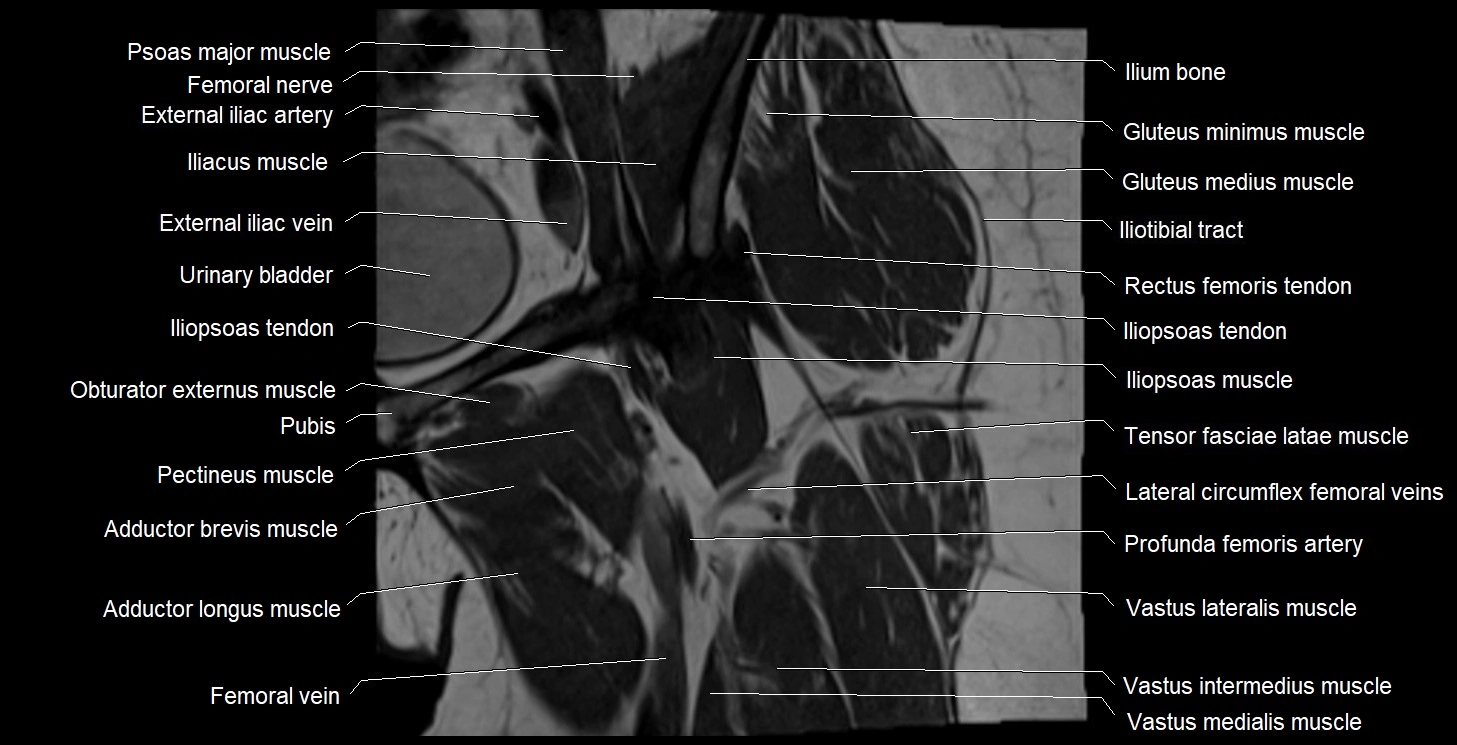

- Adductor brevis muscle

- Adductor longus muscle

- External iliac artery

- External iliac vein

- Femoral nerve

- Femoral vein

- Gluteus medius muscle

- Gluteus minimus muscle

- Iliopsoas muscle

- Iliopsoas tendon

- Iliotibial tract

- Ilium bone

- Lateral circumflex femoral veins

- Pectineus muscle

- Psoas major muscle

- Rectus femoris muscle

- Rectus femoris tendon (Proximal tendon of rectus femoris)

- Tensor fasciae latae muscle

- Urinary bladder

- Vastus intermedius muscle

- Vastus lateralis muscle

- Vastus medialis muscle